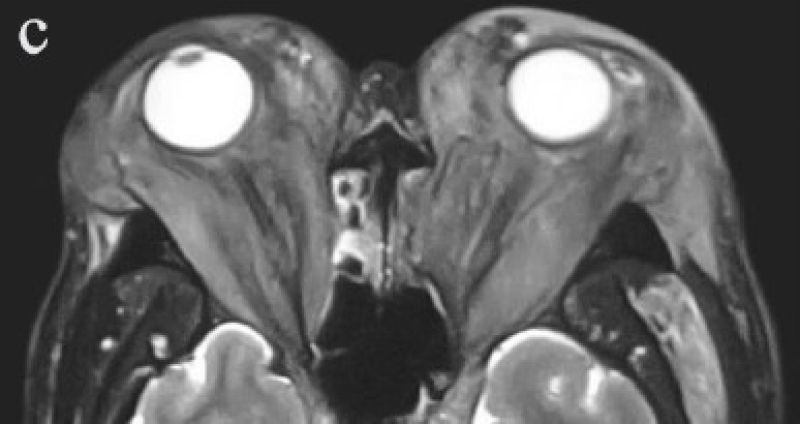

Görkem Arıca, İsmail Yılmaz, Doğu Küçüksüleymanoğlu, et al.

Arıca et al. reported that in fetuses with fetal growth restriction, decreased umbilical venous perfusion is accompanied by a compensatory increase in main portal vein flow, whereas the type of umbilicoportal anastomosis does not significantly affect main portal vein hemodynamics.